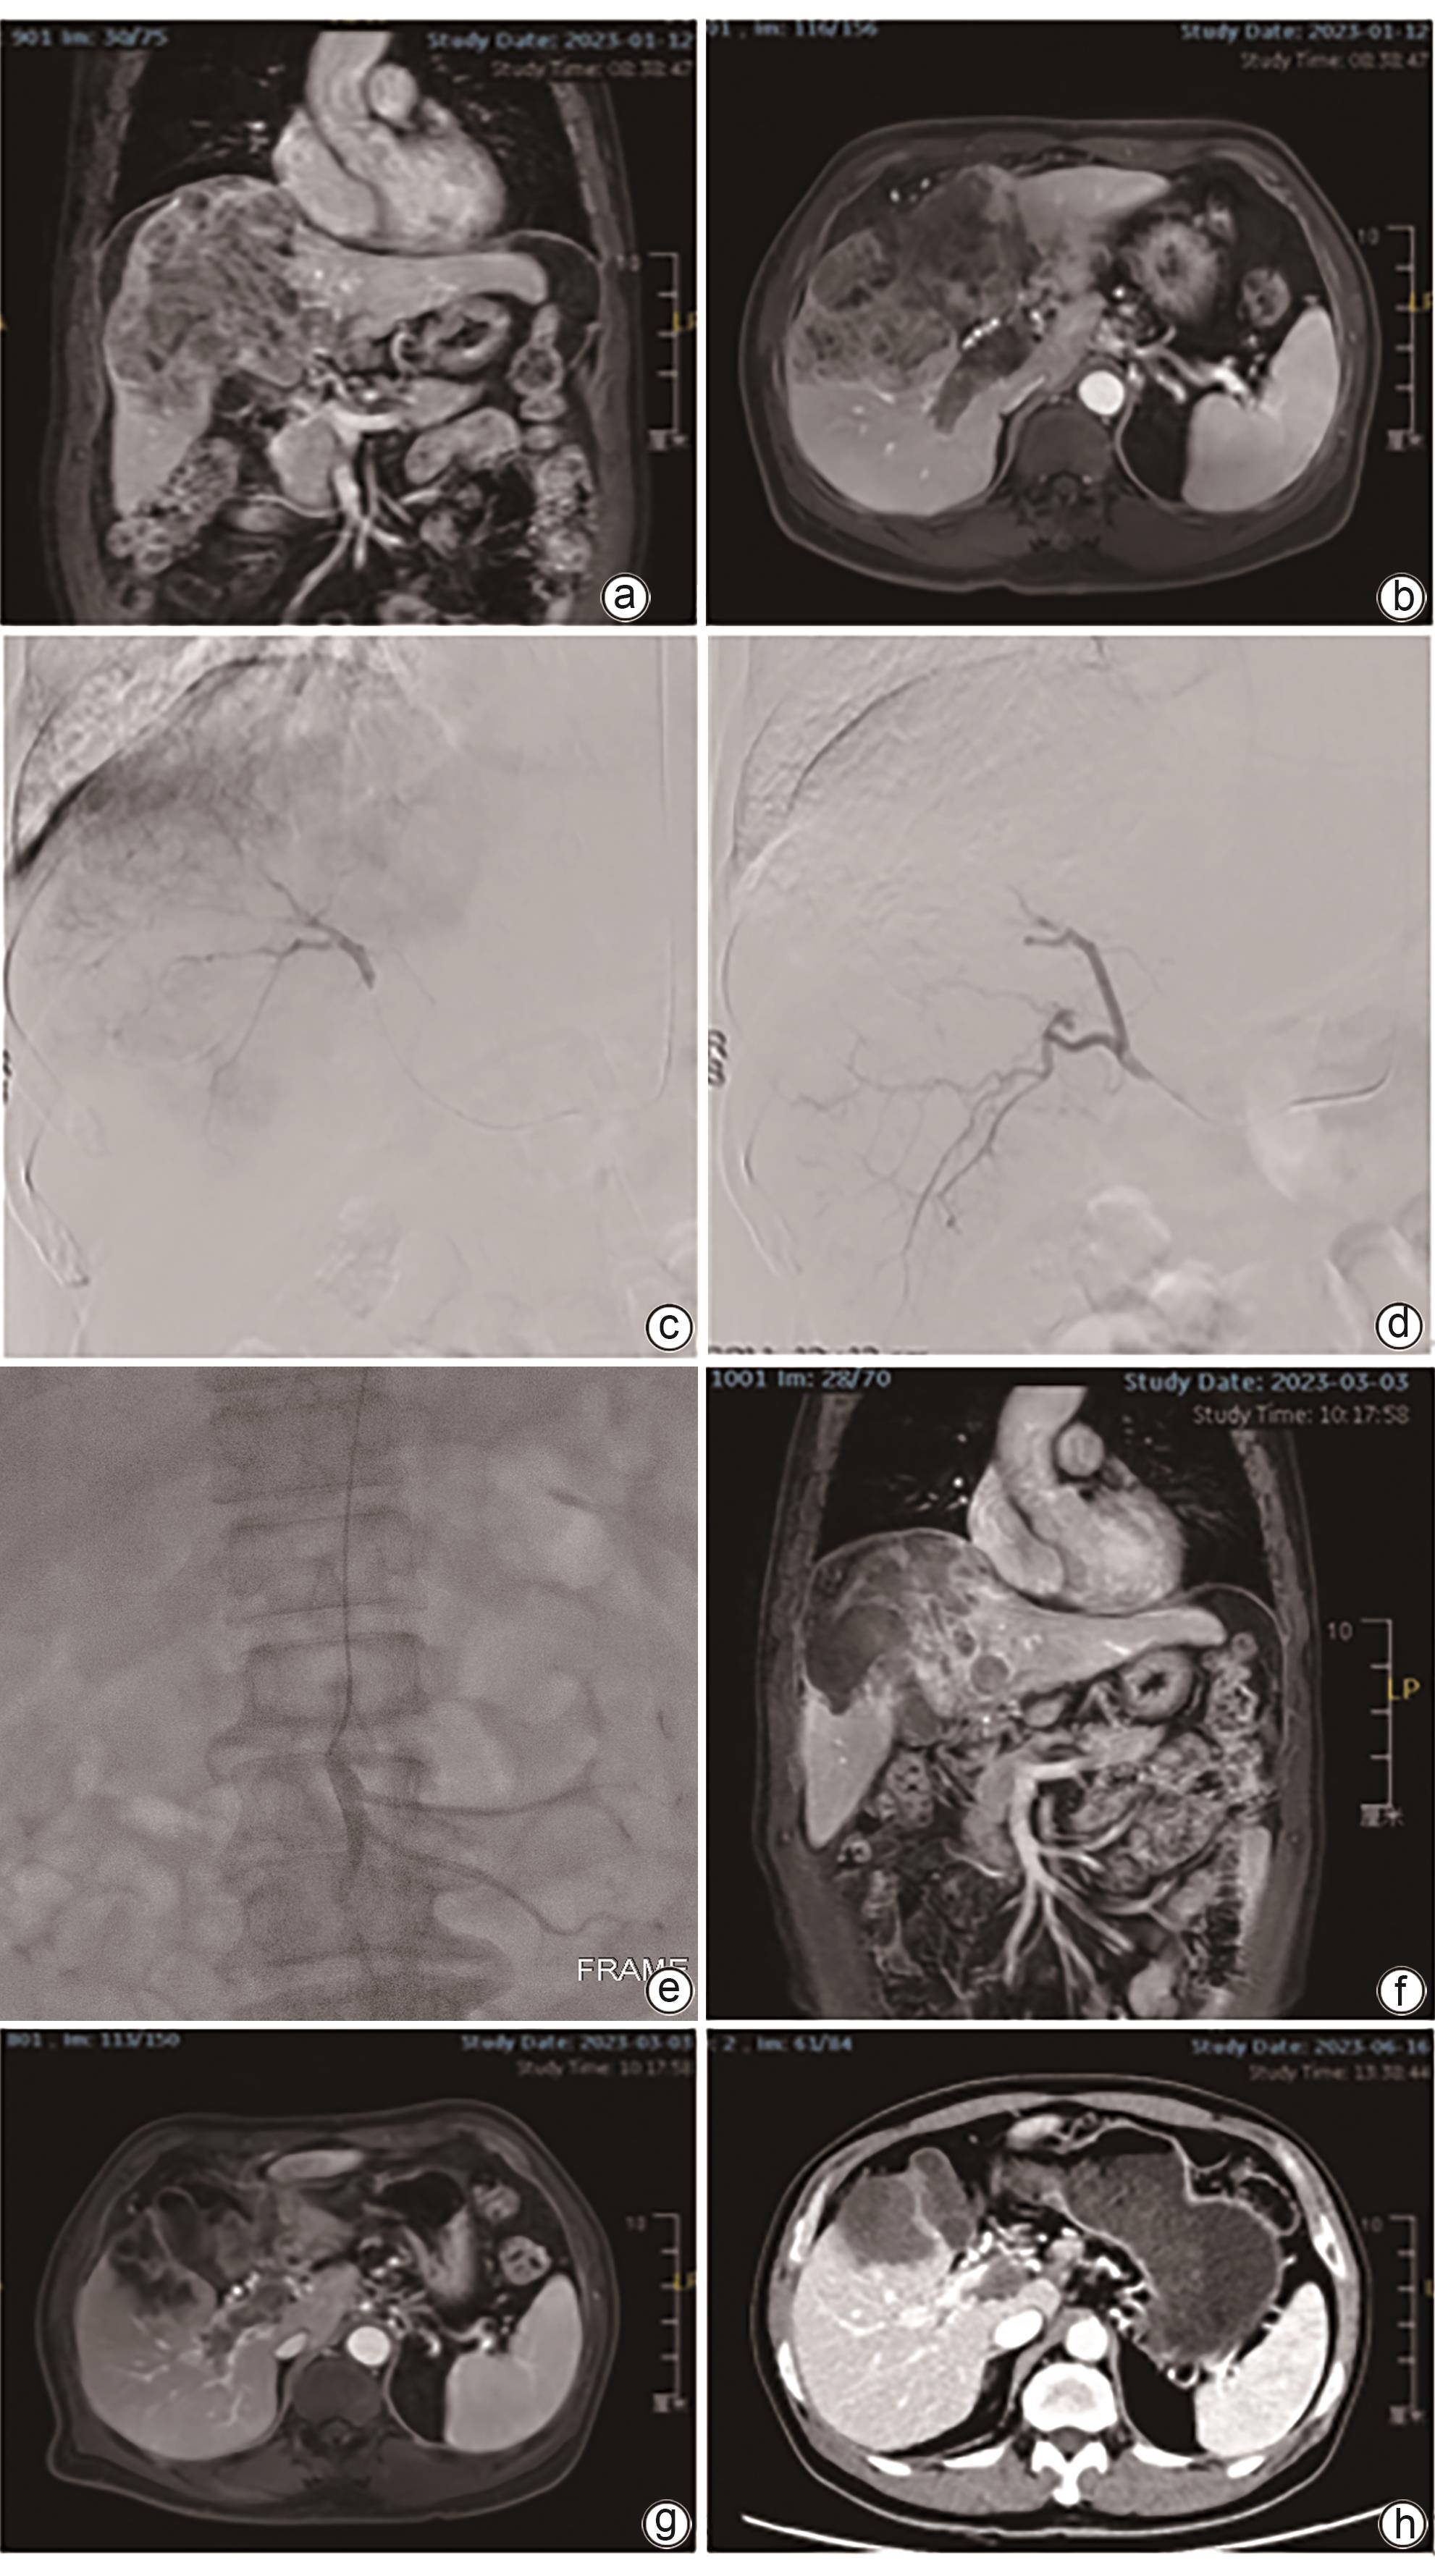

载药微球经导管动脉化疗栓塞术联合肠系膜上动脉灌注化疗治疗肝细胞癌合并门静脉癌栓的效果分析

黄乾鑫, 神斌, 肖晋昌, 高志康, 吕墩涛, 李艳, 徐浩, 张庆桥

2024, 40(12): 2457-2463. DOI: 10.12449/JCH241216

摘要(1437) HTML (311) PDF (1735KB)(66)

摘要:

目的  对比分析载药微球经导管动脉化疗栓塞术(D-TACE)联合肠系膜上动脉灌注化疗与单纯D-TACE治疗肝细胞癌合并门静脉癌栓(PVTT)的效果。  方法  回顾性分析徐州医科大学附属医院2022年1月—2023年12月行介入治疗的肝细胞癌合并PVTT的患者资料,其中采用D-TACE联合肠系膜上动脉灌注化疗的患者15例(观察组)。按1∶1进行倾向性匹配后入选单纯D-TACE治疗的患者15例(对照组)。术后1、2、3个月及以后每3个月行上腹部增强MRI评估肝脏肿瘤及PVTT情况。对比分析两组患者客观缓解率(ORR)、疾病控制率(DCR)。计量资料两组间比较采用成组t检验或Mann-Whitney U检验,术前、术后资料比较采用配对t检验或Wilcoxon检验。计数资料两组间比较采用χ2检验。采用Kaplan-Meier曲线计算累积生存率,并使用Log-rank检验比较两组差异。  结果  两组患者治疗技术成功率100%,术后均无严重并发症。全部患者随访3~26个月,平均(10.5±6.7)个月。术后3个月,观察组和对照组肝脏肿瘤的ORR(73.3% vs 53.3%)和DCR(93.3% vs 80.0%)差异均无统计学意义(P值均>0.05);观察组PVTT的ORR(46.7% vs 13.3%)和DCR(100% vs 73.3%)均显著高于对照组(χ2值分别为3.968、4.615,P值分别为0.046、0.032)。观察组和对照组患者累积3、6、12个月无进展生存率分别为93.3%、86.2%、68.9%和80.0%、62.2%、24.9%(P=0.028);累积3、6、12个月总生存率分别为100%、88.9%、88.9%和93.3%、85.6%、70.0%(P=0.340)。  结论  与单纯D-TACE相比,D-TACE联合肠系膜上动脉灌注化疗在治疗肝细胞癌合并PVTT方面显示了更好的近期疗效。